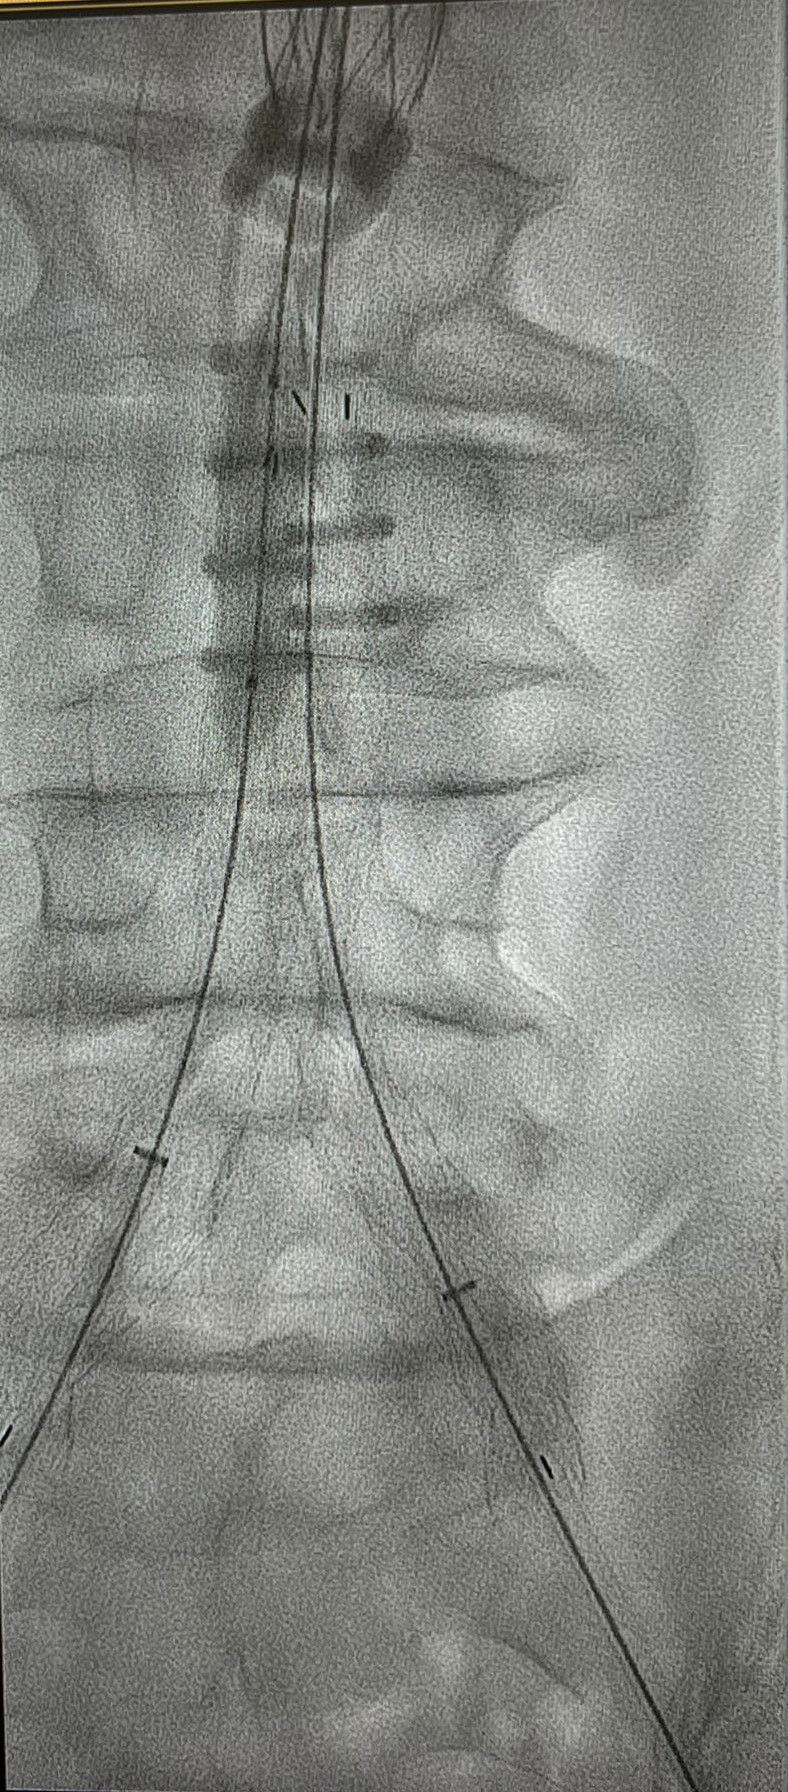

În Clinica de Chirurgie Cardiovasculară a UMF Carol Davila de la Spitalul Clinic de Urgență București (Floreasca) au fost rezolvate săptămâna trecută trei cazuri de anevrism de aortă abdominală infrarenală, dintre care unul rupt.

Soluția adoptată a fost non-chirurgicală: s-a realizat implantarea unor stentgrafturi endoaortice pecutanat (fără incizii chirurgicale) – EVAR, se arată pe pagina de Facebook Chirurgie cardiovasculară Floreasca.

Procedurile au fost realizate de prof. univ. dr. habil. Horațiu Moldovan (foto), Șeful Clinicii de Chirurgie Cardiovasculară, împreună cu colegii chirurgi, cardiologi intervenționali și anesteziști: